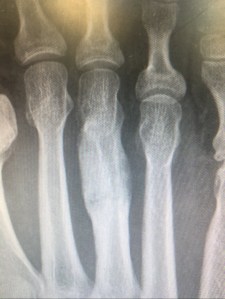

You may remember that I had a bot of a health scare back in January. Shortly after that, I had the return of the foot pain that I had suffered from in November last year, all be it a few toes further along. I decided to skip the GP and go and see a podiatrist and he referred me to get X-rays at the local hospital.

It turns out that the injury last year was a stress fracture as, apparently, is obvious by the below picture! Apparently it has healed perfectly, despite the fact I was told it was ‘probably a strained ligament or something’ but they had no idea what was wrong with my new injury and suggested limping or not whinging.